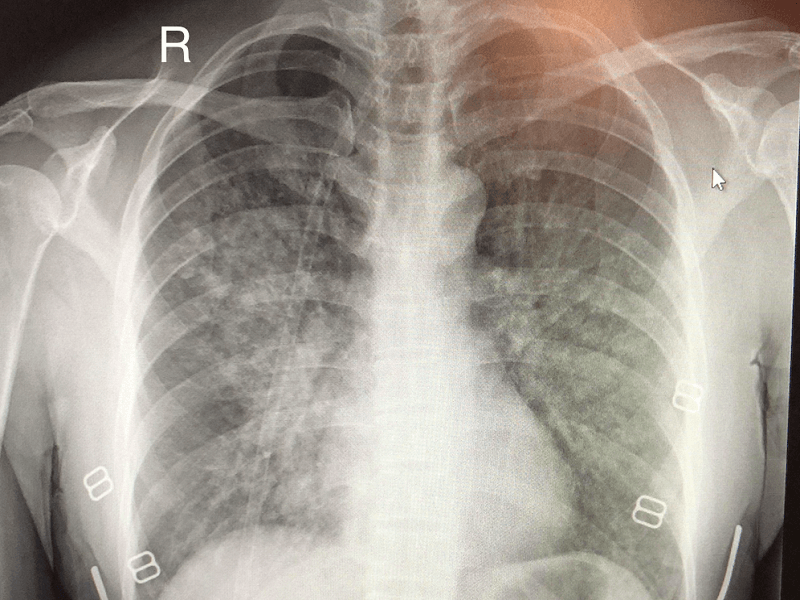

أولاً – عمل الفحوصات الطبية

والتي تتمثل في:-

- عمل فحوصات دم كاملة على وظائف الكُلى والكبد، بالإضافة إلى صورة دم كاملة.

- أشعة متخصصة على الصدر.

- عمل موجات صوتية للقلب.

- عمل أشعة مقطعية لمعرفة سبب تجمع الماء على الرئة.

- قد يضطر الطبيب إلى سحب عينة من الماء بواسطة أشعة الموجات الصوتية لفحصها معمليًا.

- تنظير صدري من أجل الحصول على عينة من تجمع السوائل في الغشاء البلوري.